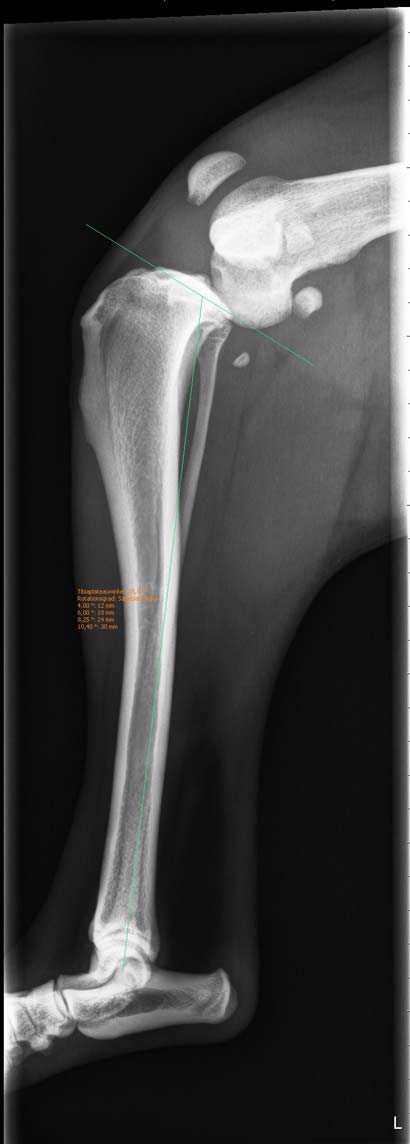

Zuerst wurde planmäßig ein Kunstband in das Knie eingesetzt, sowie eine TPLO vorgenommen. Bei der Hüft-OP konnte dann der Fermurkopf leider nicht in die Pfanne zurückgeführt werden, da er aufgrund der Dauer der Verletzung zu steil verwachsen war (Fehlstellung). Es wurde dann eine Fermurkopfhalsresektion durchgeführt. Danach zeigte Momo noch eine unphysiologische Innenrotation des Kniegelenks. Daher musste dann zur Stabilisierung des Außenbandes ein Faden eingesetzt werden.

In der heutigen Untersuchung wurde festgestellt, dass nicht nur Momo´s Bänder im Knie gerissen sind, sondern dass sie auch noch eine Beckenluxation hat (der Knochen ist aus der Pfanne gesprungen).